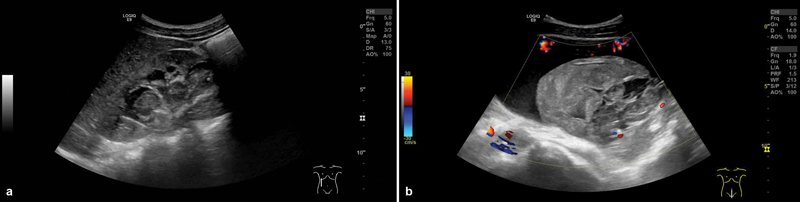

Arterio-ureteral fistula (AUF) is a rare condition affecting nearby adult-only patients. Patients usually present with hematuria, often starting as intermittent hematuria which frequently increases, and may lead to hemorrhagic shock. Without rapid diagnosis and prompt treatment, AUF can be lethal. Risk factors for developing an AUF include a history of pelvic surgery mainly due to cancer, a history of pelvic radiation, a history of vascular surgery, or chronic indwelling ureteral stents (CIUS). Imaging to confirm diagnosis includes angiography, computed tomography (CT) scan, or retrograde pyelography, although AUF may be missed. Therefore, even if imaging is negative, the presence of hematuria of unexplained origin in combination with mentioned risk factors is highly suspicious for AUF and must be excluded. We report the case of a 16-year-old male patient who presented with a new onset of intermittent hematuria to our emergency room. The patient's history included previous pelvic surgery for resection of ganglioneuroma 6 years ago with bilateral replacement of the iliac artery and postoperative acute kidney failure with reconstruction of both ureters and CIUS. After the initial uneventful postoperative follow-up over 5 years, another Double J (DJ) catheter had to be placed into the right ureter due to hydronephrosis. Six weeks later, the patient presented with intermittent hematuria. Despite negative imaging, we performed immediate surgical exploration confirming the diagnosis of AUF. To the best of our knowledge, this is the first case of AUF under the age of 18 years reported in the literature. In conclusion, in patients with macrohematuria and a history of the abovementioned risk factors, AUF has to be kept in mind and must be reliably excluded.